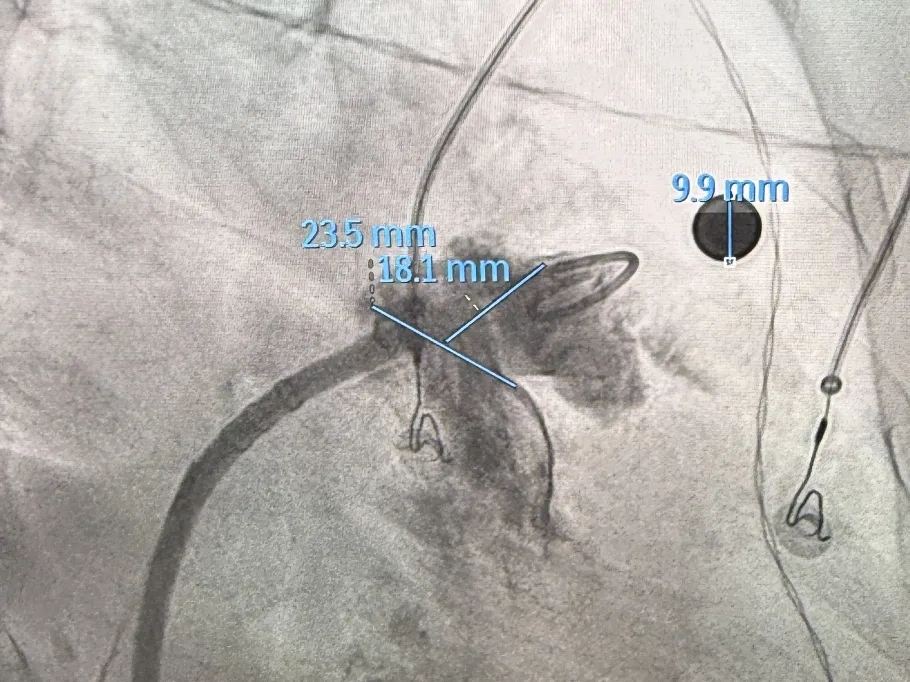

术中DSA肝位造影:双分叶鸡翅型左心耳

肝位造影,心房侧显影,轴向偏前,下缘早分叶

开口23.5mm,深度18.1mm

左心耳开口偏小,术前CT三维重建测量工作位左心耳大小20.1*17mm,正足位20度左心耳大小20.3*15.5mm,术中肝位造影确认左心耳大小为23.5*18.1mm。

本次病例为双分叶鸡翅型心耳,深度18.1mm,开口23.5mm,最终使用LAFDQ-26进行左心耳封堵。房间隔穿刺时考虑本病例心耳开口上缘距左上肺静脉下缘较近,属低位双分叶鸡翅型心耳,穿刺位点选择偏下靠后,良好的穿刺位点更利于手术操作轴向;封堵器输送时,保证心耳封堵轴向往上叶,方便术中调整封堵器形态,减少封堵难度,提高手术安全性。术中造影发现左心耳内部存在隐窝结构,术者选择使用MemoLefort进行封堵。